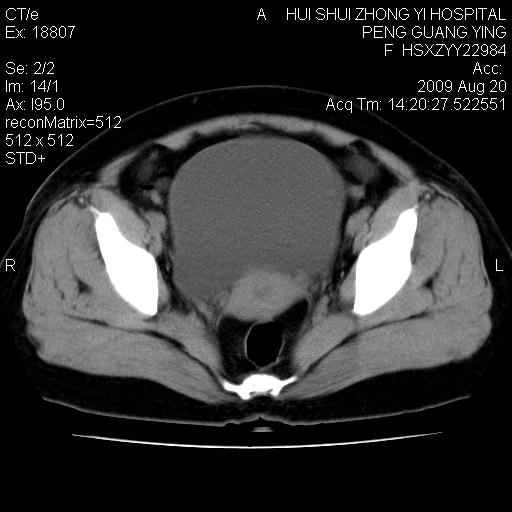

标题: CT21707:女,42岁,因发现下腹部包块2月。 [打印本页]

标题: CT21707:女,42岁,因发现下腹部包块2月。

增强看看,倾向于子宫肌瘤并囊变或腺肌征,宫腔少量积液。

考虑 1 卵巢囊腺瘤 2 子宫肌瘤。

目前的影像表现显示肿块位于腹腔及盆腔,但具体定位,分清来源较困难,是否来源于卵巢、子宫无法定论,子宫直肠及子宫膀胱周围脂肪间隙尚较清晰,如果患者有过腹腔好或者盆腔手术史,也可以形成不典型的血中,最好手术后定为定性,我期待结果。

软组织密度,与子宫一致。双侧卵巢形态、密度好,不支持来源于卵巢。